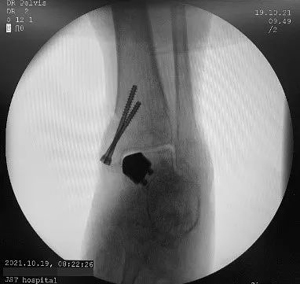

消毒铺单完毕后,武勇主任熟练地进行了胫骨V型截骨,显露关节,找到病变的区域,将事先设计好的导板贴附在距骨的病变区,按照截骨导板,精准地铲除了病变的区域,装入试模假体,对截骨的底部进行了细微地调整,再次放入试模发现贴合良好,于是将3D打印的假体置入,克氏针固定截骨端,活动踝关节,确定周围组织无撞击以及假体初始稳定性良好,透视关节对合良好,遂拧入两枚空心钉固定,逐层缝合手术结束。手术过程非常顺利,用时不到1个小时。

手术中情况